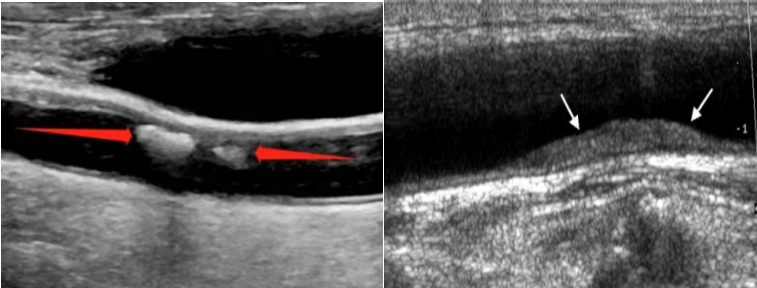

颈动脉超声是诊断评估动脉壁病变的有效手段之一,利用超声波技术,观察血管走行、内-中膜是否增厚、有无斑块形成、斑块的回声性质、是否有血管狭窄及狭窄程度、有无闭塞等详细情况,并对病变进行测量和定位,同时对动脉的血流动力学结果进行分析。所谓“颈动脉超声”说的是颈动脉系统,根据部位不同可分为颈总动脉、颈内动脉、颈外动脉,通常我们还会同时检查双侧椎动脉及锁骨下动脉。

二、什么是颈动脉斑块?

颈动脉斑块是颈动脉最常见的动脉病变,通俗来说,颈动脉斑块就像水管里的水锈。受各种因素的影响,人体动脉血管会逐渐老化、硬化,血管内的“杂质”随着血流的流动不断地沉积到血管壁上,在血管壁上形成增厚的凸起,这就是斑块形成的过程。全身的动脉血管都可能“长斑”,其中尤以颈动脉斑块危害最大!